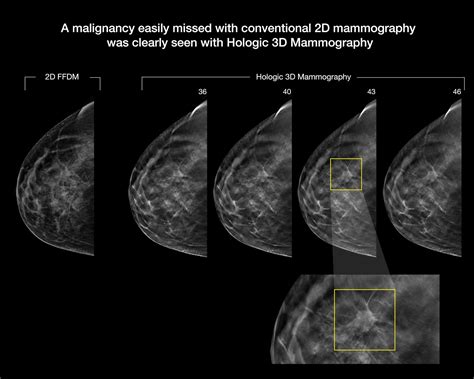

For decades, standard 2D digital mammography was the gold standard. However, 2D images take a flattened view of the entire breast, which can lead to overlapping tissues that look like suspicious spots. A Dense Breasts 3D Mammogram, clinically known as digital breast tomosynthesis, works differently by taking multiple images from various angles. These images are then reconstructed into a series of thin “slices,” allowing the radiologist to scroll through the breast tissue layer by layer.

The primary advantage of opting for a 3D mammogram when you have dense tissue is the reduction of diagnostic uncertainty. Because radiologists can look through the tissue rather than looking at a flat projection, they are less likely to mistake overlapping normal tissue for a lesion. This leads to several clinical benefits:

• Improved Cancer Detection: Studies show that 3D imaging finds invasive cancers more reliably than 2D imaging.

The interpretation of a Dense Breasts 3D Mammogram requires specialized training. Radiologists must analyze hundreds of individual slices to ensure no subtle changes are missed. By utilizing the 3D data, they can isolate specific areas of concern that might have been buried under dense, fibroglandular tissue in a 2D scan. This technological precision empowers medical professionals to provide more confident assessments, ultimately leading to better peace of mind for the patient.